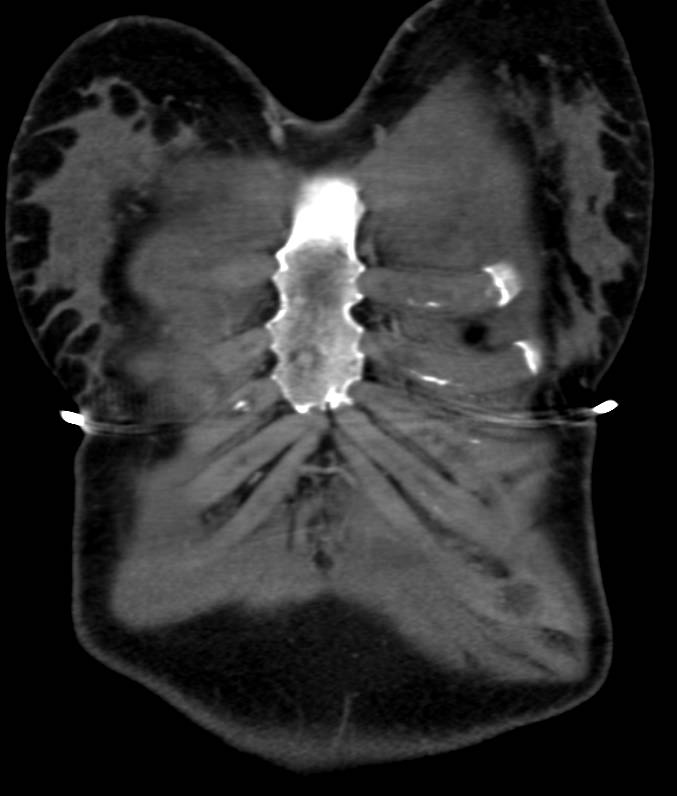

Marfan Syndrome with Dural Ectasia and Aortic Dissection